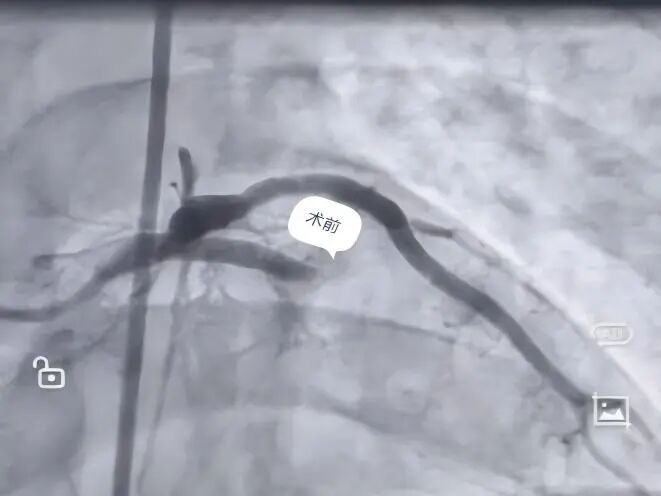

胸痛突袭,生命告急 “心”危机终化险为夷 ❤️❤️❤️ 9月的一天,36岁的朱先生突然感到胸部持续剧痛。当地卫生院医生第一时间完成心电图检查,判断可能是“急性心肌梗死”,并立即启动与贵州航天医院胸痛中心的联动。 在转诊救护车上,急救人员已遵照胸痛中心的指导为朱先生用上了必要的药物。可就在车辆抵达贵州航天医院急诊科的那一刻,险情骤然升级——朱先生出现了呼吸心跳骤停、反复室颤!急诊科团队立即就地展开抢救,通过持续心肺复苏、紧急气管插管、呼吸机辅助通气及十余次电除颤等紧张有序的处置,朱先生终于恢复了自主心跳,待其生命体征趋于平稳后,便被火速转运至导管室进行后续救治。 在心血管内科、导管室、麻醉科的通力配合下,冠状动脉造影很快找到了“元凶”——心脏的一根重要血管(前降支)被完全堵死。与家人充分沟通后,团队迅速为朱先生开通了堵塞的血管,并植入一枚支架。从入院到血管开通,这场关键手术仅用了45分钟。术后,经过多学科团队两周的精心照护,朱先生恢复良好,现已顺利出院。 这场“接力赛”为何能成功? 1.基层“哨兵” 乡镇医生准确识别、快速转诊,抢下最初宝贵时间。 2.120“生命快车” 途中持续监护与用药,搭建起移动的生命桥梁。 3.医院“专家团队” 多科室紧密协作,应对突发状况,以精湛技术打通生命通道。 【健康小课堂】 ▶如何识别心梗信号? 典型表现: 突发性、压榨性的胸骨后疼痛,可能放射到左肩、背部、下颌或手臂,常伴大汗、恶心、濒死感。 不典型表现(尤其需警惕!): 对于部分人群,可能只表现为莫名的乏力、头晕、气短、恶心呕吐,甚至只是牙痛、喉咙发紧或上腹痛。 ▶记住两个“120”,关键时候能救命! 一旦怀疑是心梗,立即拨打120急救电话!不要自行驾车或打车去医院,以免途中发生意外,争取在120分钟内开通堵塞的血管。 ▶防大于治,别拿生命开玩笑! 预防永远是第一位的。高血压、高血脂、糖尿病等慢性疾病,以及吸烟、熬夜、缺乏运动、饮食不节等不健康生活习惯,都会默默损害血管健康。这就像一条原本光滑的管道,长期受损后会变得粗糙,杂质(如血脂)就容易沉积,形成“水垢”(动脉粥样斑块)。一旦“水垢”破裂,身体就会在破口处快速“打补丁”(形成血栓),这个“补丁”若完全堵死血管,心肌梗死就发生了。 时间就是心肌,时间就是生命。关注心血管健康,从识别信号、及时求助和改善生活习惯开始。 贵州航天医院 心血管内科专家简介 沈万贵 心内科党支部书记、主任,副主任医师 临床擅长:从事临床工作约33年,对冠心病,高血压病,各种心肌病等疾病的诊治以及内科疑难杂症疾病的诊疗具有丰富诊疗经验,累计实施冠心病、外周血管等疾病的介入手术诊疗过万例。擅长于冠脉复杂病变的介入手术治疗、肾动脉狭窄介入手术、下肢深静脉血栓的介入手术治疗。 贵州省医学会心血管病分会常务委员、贵州省心脏病康复医学会常务委员,遵义市医学会心血管病分会副主任委员,西南高血压病管理委员会常务理事,贵州省冠心病组委员;发表学术论文20余篇。 张羽坤 中共党员,心血管内科副主任,主任医师,硕士研究生 临床擅长:具备心血管疾病心律失常介入(导管消融及植入器械)国家级手术资质,参与各类心脏介入手术6000余例。以第一作者在国内核心期刊发表医学论文10余篇,主持市级科研项目1项。 曾先后前往贵州省人民医院、国家心脏中心北京阜外心血管病医院学习深造(2017年11月至2018年11月参加第二期黔医人才计划并获得优秀学员称号),2022年获得贵州省“第二届最美劳动者”称号。 中国医疗保健国际交流促进会心律与心电分会第三届委员,中国老年医学学会心血管病分会第二届委员会基层委员,贵州省心电生理与起搏分会委员,贵州省中西医结合学会心血管专业委员会委员,遵义医学会心血管病学分会常委,遵义市医学会(第六届)理事会理事,遵义市健康科普专家;是遵义医科大学科技学院及遵义医药高等专科学校兼职教师。 李树刚 中共党员,心血管内科主任医师 临床擅长:具备冠心病介入手术治疗资质,对心内科各种常见病、多发病及急性冠脉综合征疾病具有丰富的临床诊治经验,完成各项冠心病介入治疗6000余台。 毕业于遵义医学院临床医学专业,以第一作者在国内核心期刊发表医学论文数篇,主持并结题市级科研项目1项;遵义市医学会心血管病分会委员,遵义市健康科普专家成员。 刘忠凤 中共党员,心血管内科副主任医师 临床擅长:对结构性心脏病超声心动图的判读及解析、结构性心脏病的诊疗有丰富的临床诊疗经验;擅长心血管常见多发病及难治性心衰的诊治、恶性心律失常的抢救。 遵义市医学会心血管病分会委员,遵义市医学会内分泌暨糖尿病分会委员,遵义市医学会骨质疏松暨骨矿盐疾病学分会委员;曾前往贵州省人民医院超声心动图室、四川大学华西医院超声科进修学习超声图;发表省级期刊数篇,参与结构性心脏病术中超声指导。 李茂春 心血管内科副主任医师 临床擅长:1995年毕业于遵义医学院临床医学系,从事临床工作28年,熟练掌握高血压、冠心病等心血管疾病的诊治及危急重症患者的救治,擅长糖尿病、甲状腺功能亢进、代谢综合征等内分泌代谢性疾病的诊治,在多年的临床工作中对内分泌代谢疾病、心血管疾病的诊治中积累了丰富临床的经验。 贵州省医学会内分泌暨糖尿病学分会第七届委员会甲状腺学组组员,遵义市内分泌暨糖尿病学分会第一届委员会常务委员,贵州省康复医学会骨内科专业委员会遵义地区分会常务委员。多年来在省内外期刊发表论文数十篇。 胡兴丽 心血管内科副主任医师 临床擅长:对心血管及内分泌相关常见疾病的诊治及抢救工作具有丰富的临床经验,擅长心血管及心律失常的介入手术。 2009年毕业于遵义医学院临床医学专业,临床工作10余年,有外出进修 CCU 学习经历,发表论文数篇。云贵川高血压联盟委员。 杨 菊 中共党员,心血管内科副主任医师,硕士研究生 临床擅长:具备心血管疾病冠脉介入手术资质,参与各类冠心病介入手术3000余例。 遵义市医学会心血管病分会委员,多次获得“优秀党员”、“优秀帮扶对象”、“优秀带教老师”等荣誉称号,遵义医药高等专科学校及遵义医科大学科技学院兼职教师;以第一作者在国内核心期刊发表医学论文数篇,主持并结题市级科研项目1项。 张 禹 心血管内科副主任医师 临床擅长:熟练掌握冠心病、心律失常、高血压、心力衰竭、风湿性心脏病、扩心病等心血管疾病诊治,以及急、危、重症病人的救治。 2017年在重庆第三军医大学新桥医院心内科进修学习,2018年贵州省人民医院进修心律失常介入治疗,取得心血管疾病心律失常介入(导管消融)国家级手术资质,参与冠脉介入、射频消融、起搏器置入等心内科介入手术4000余例;是遵义市医学会心血管病分会委员。 贵州航天医院 心血管内科简介 基本情况 贵州航天医院心血管内科编制床位60张,配置了29台24小时动态心电图、110台24小时动态血压、心脏除颤仪、监护仪、输液泵、微量注射液,同步12导联、18导联心电图机、临时心脏起搏器、床旁血糖仪、主动脉内球囊反搏、食道超声、血管内超声诊断仪及DSA心血管诊疗等。 学科、专科建设 近年来成功获批胸痛中心、房颤中心、儿童先天性心脏病定点救治单位授牌;是遵义市临床重点专科、远程心电示范中心、高血压慢病管理示范中心。 科室诊疗范围 开展了急诊冠脉介入诊疗,冠脉复杂病变介入术、冠状动脉斑块旋磨术、心脏再同步治疗起搏器植入术、心脏再同步治疗除颤器植入术、射频消融术【心房颤动(导管消融、冷冻消融)、心房扑动、房性心动过速、室性心动过速、室性早搏】、结构性心脏病介入治疗【房间隔缺损(卵圆孔未闭)封堵术、室间隔缺损封堵术、动脉导管未闭封堵术、冠状动脉瘘封堵术、左心耳封堵术等】、临时起搏器植入术、常规永久起搏器植入术(双腔、单腔)、下肢动静脉造影术、下腔静脉滤器植入及取出术、自主肾上腺静脉采血、颈动脉支架植入术、外周动脉支架植入术、肾动脉支架植入术等,积极开展冠脉内超声检查、FFR、OCT、心脏射频三维手术、房颤一站式治疗(房颤射频消融术+左心耳封堵术)、主动脉瓣介入术等,并邀请院外专家指导成功开展腹主动脉支架植入术。